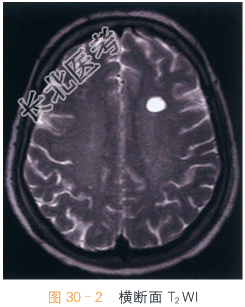

女,28岁,头痛、头晕4月余。

读片分析:头颅横断面T₁WI,T₂WI显示左侧额叶均匀的长T₁WI,长T₂WI信号,边界清晰,周围脑实质未见水肿;横断面、矢状面T₁W增强显示左侧额叶病灶未见明显强化。结合病史,患者考虑为神经上皮囊肿。